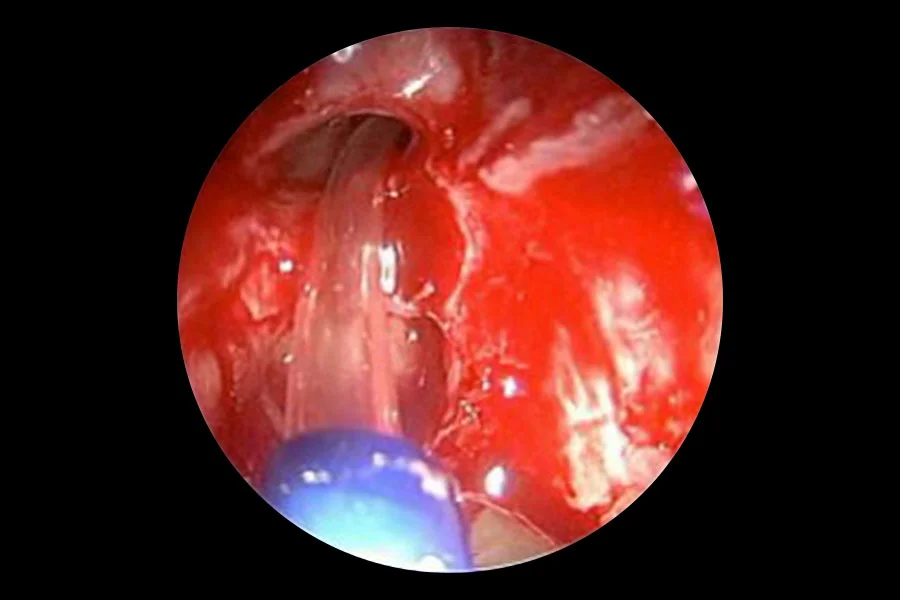

Balloon sinuplasty is an advanced, tissue-preserving procedure designed to relieve blocked sinuses in patients with chronic or recurrent sinusitis. Using endoscopic guidance, a soft balloon device is introduced into the natural sinus openings and inflated to gently remodel and widen them, restoring normal ventilation and drainage.

This technique avoids cutting or removal of bone and mucosa, making it less invasive than conventional sinus surgery. It is typically performed as a short-stay or day-care procedure with rapid recovery for patients contraindicated for conventional surgeries.